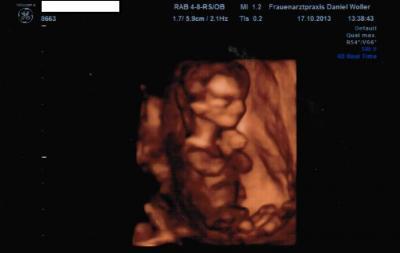

Mein 3D-Bildchen bei 12+0 :)

Wie versprochen hier noch schnell das Bild vom letzten Ultrachall gestern :)